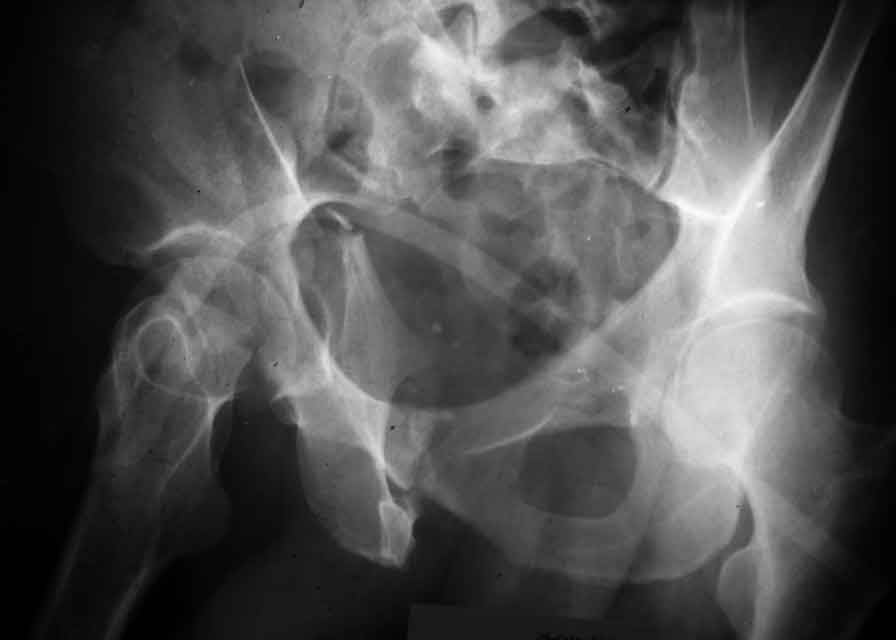

I am sending another iliac view, and a marked version of the AP I already sent. In this AP, the

proximal part of the greater sciatic notch as well as the distal parts of the ilioischial and iliopubic lines are marked with a grey interrupted line. A white interrupted line marks what could be an exit through the obturator foramen, or so I assume.